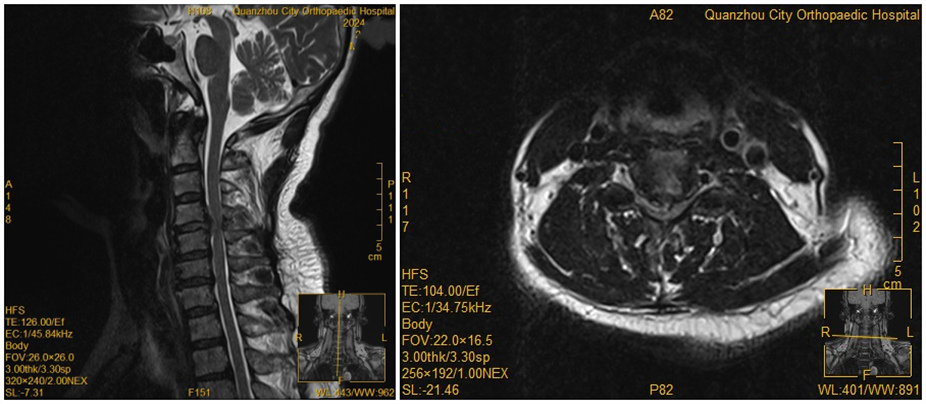

[疾病专题] 【正骨技术】脊柱严重畸形,麻醉如何“破局”?我院成功护航患者完成髋关节 日期:2025-12-11 15:19:00 点击: 好评:0